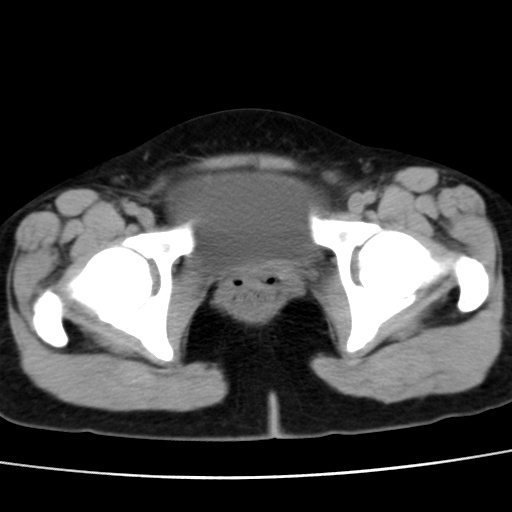

子宫多发肌瘤吗

多发性子宫肌瘤.

考虑多发子宫肌瘤,子宫直肠窝双囊性占位,另直肠周围脂肪密度增高,不知有何病史

支持考虑多发子宫肌瘤~!子宫直肠陷凹积液?

支持考虑多发子宫肌瘤~!子宫直肠陷凹积液!

子宫肌瘤,宫体部后方见液性密度影,是肠道还是子宫与直肠陷窝积液不好说,我觉得它的位置有点高

支持考虑多发子宫肌瘤!子宫直肠陷凹积液!

患者发热,而子宫直肠窝液性灶有明显边缘且局限且囊性,不除外为包裹性积液或脓肿

支持考虑多发子宫肌瘤,子宫直肠陷凹积液可能。

考虑多发子宫肌瘤

1)考虑子宫肌瘤可能性大。2)子宫后方囊性占位性病变,不排除卵巢囊肿可能。

考虑多发子宫肌瘤。子宫后方囊性占位性病变,不排除卵巢囊肿可能。